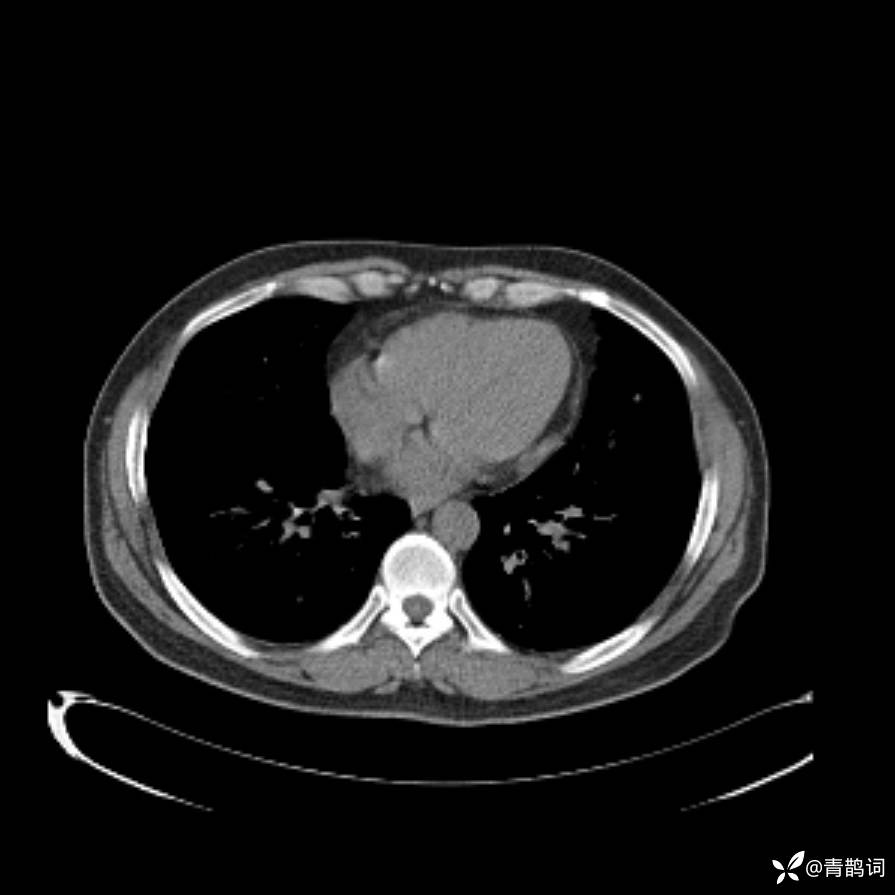

患者年龄:30岁。

患者性别:男。

简要病史:左颜面部肿胀2年,反复咳嗽咳痰,逐渐加重。

结合病史及影像学表现,期待评论区各位老师各抒己见~